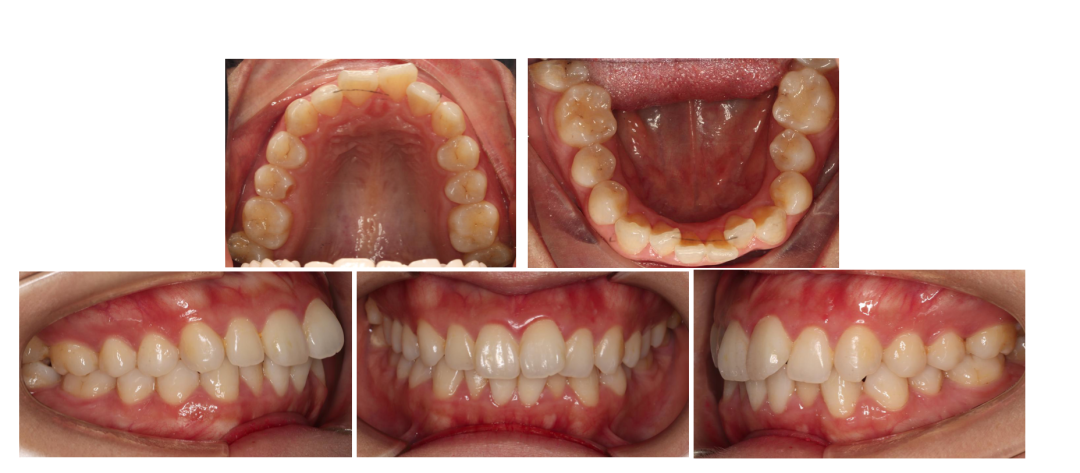

如图1-3⼝内情况所示:上下前牙轻度拥挤、上前牙唇倾、牙弓形态尚可。

如图1-4曲断片所示:28、38阻⽣,未见牙根吸收,牙周状况良好。左侧髁突见吸收。